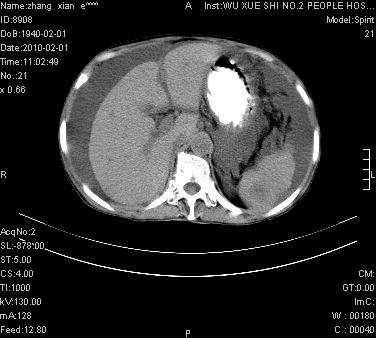

标题: CT24434:70岁 女 腹胀,腹水原因待查 [打印本页]

标题: CT24434:70岁 女 腹胀,腹水原因待查

腹盆腔大量积液,子宫增大,子宫颈增大外形不规则,内见低密度影,膀胱后壁显示不清,右腹股沟肿大淋巴结,脾脏囊性占位,子宫颈占位,子宫颈癌?建议增强。

考虑子宫癌并腹水 脾囊肿

子宫、宫颈占位?转移性腹水?肝性腹水?脾脏囊性占位,囊肿?血管瘤?淋巴瘤?

腹盆腔大量积液,子宫增大,子宫颈增大外形不规则,内见低密度影,膀胱后壁显示不清,右腹股沟肿大淋巴结,脾脏囊性占位,子宫颈占位,子宫颈癌?建议增强。支持!